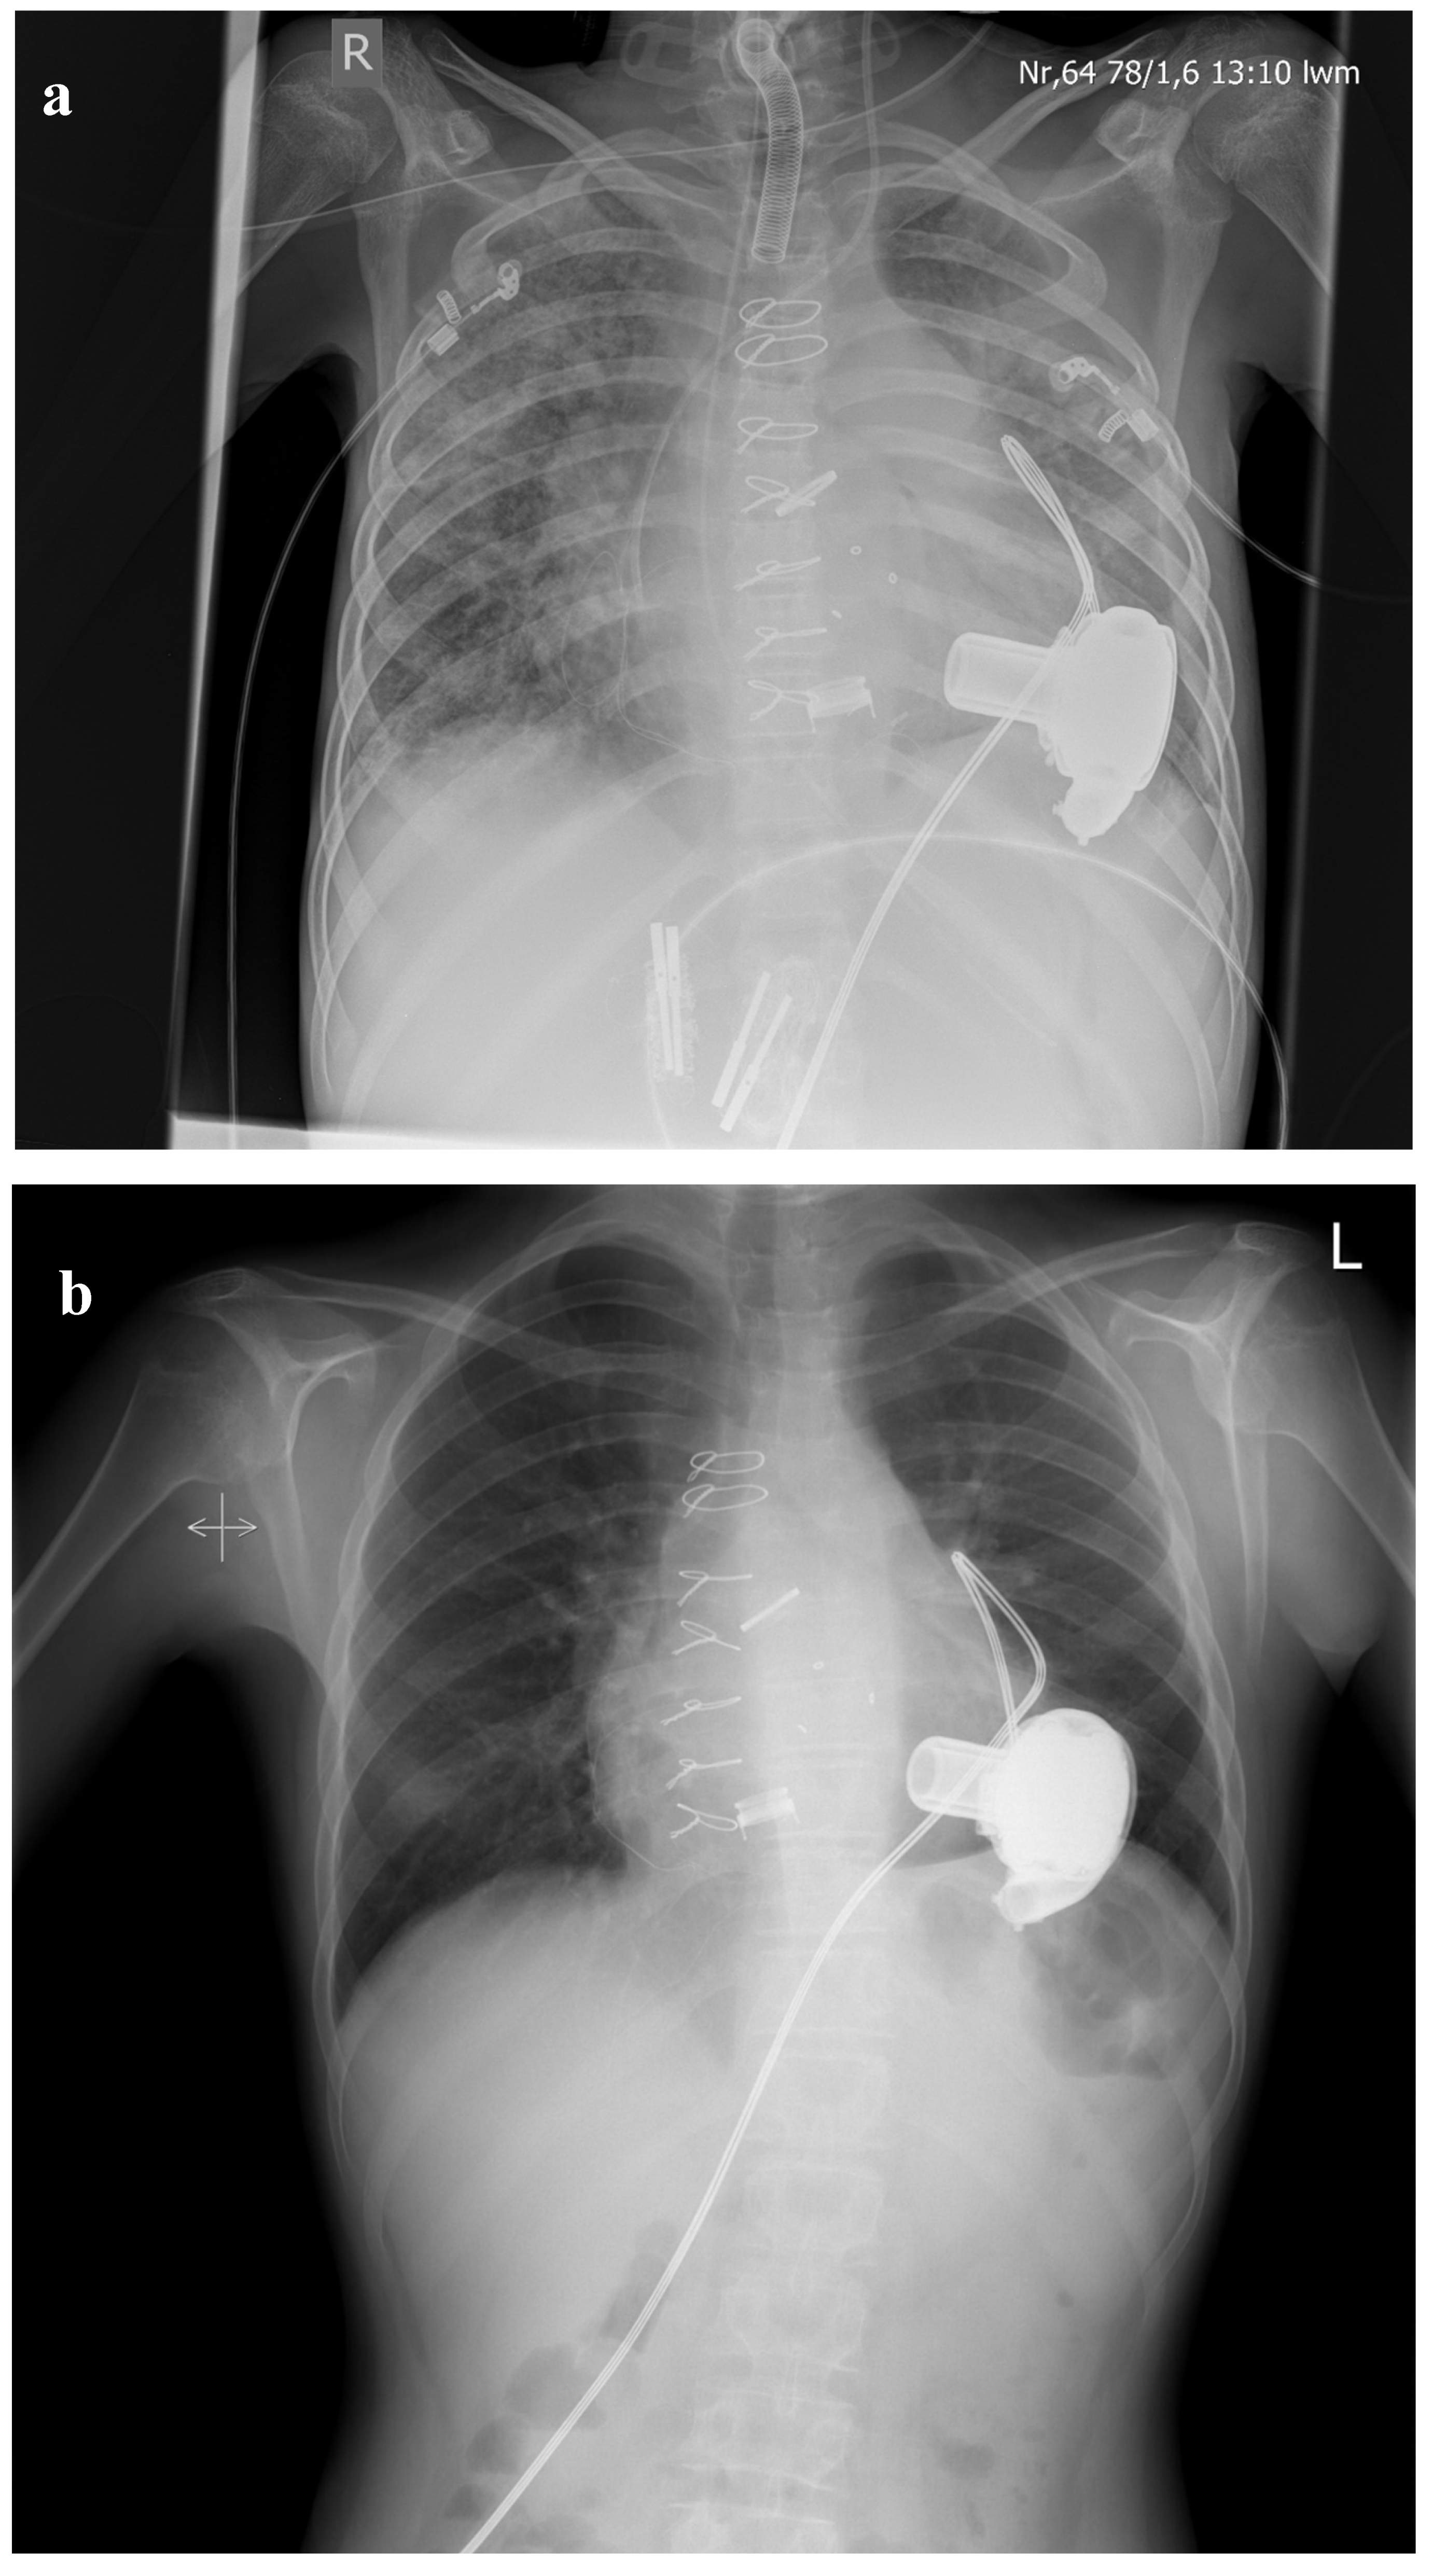

Figure 1.

(a) Chest X-ray immediately after LVAD-implantation. Fifteen-year-old male with congenital critical aortic valve stenosis after several surgical and interventional procedures (balloon valvuloplasty, 2 × aortic homograft, mechanical aortic valve (St. Jude 17 mm), mitral valve replacement (Mosaic 25 mm)) presenting with severe pulmonary hypertension (RAP mean 20 mmHG, PAP mean 58 mmHG, PAWP 23 mmHG, PVRI 20.2 WU × m2). (b) Chest X-ray 24 months after LVAD-implantation Pulmonary hypertension resolved (RAP mean 8 mmHG, PAP mean 18 mmHG, PAWP 10 mmHG, PVRI 1.3 WU × m2), and successful HTX was performed after 36 months on LVAD.